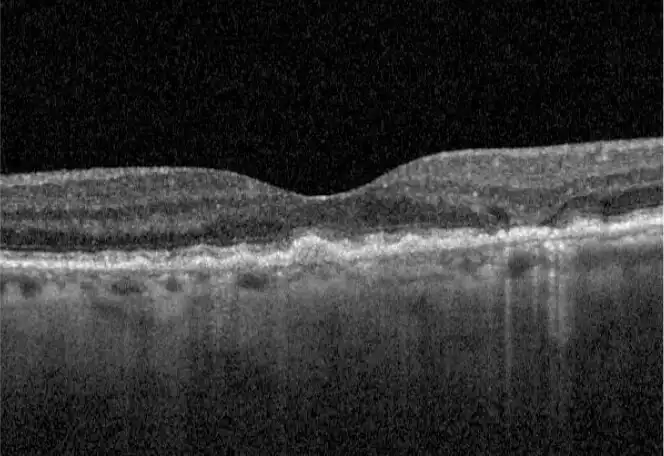

Neovascular AMD

- In clinical trials, use of IZERVAY was associated with increased rates of neovascular (wet) AMD or choroidal neovascularization (7% when administered monthly and 4% in the sham group) by Month 12. Over 24 months, the rate of neovascular (wet) AMD or choroidal neovascularization in the GATHER2 trial was 12% in the IZERVAY group and 9% in the sham group. Patients receiving IZERVAY should be monitored for signs of neovascular AMD.